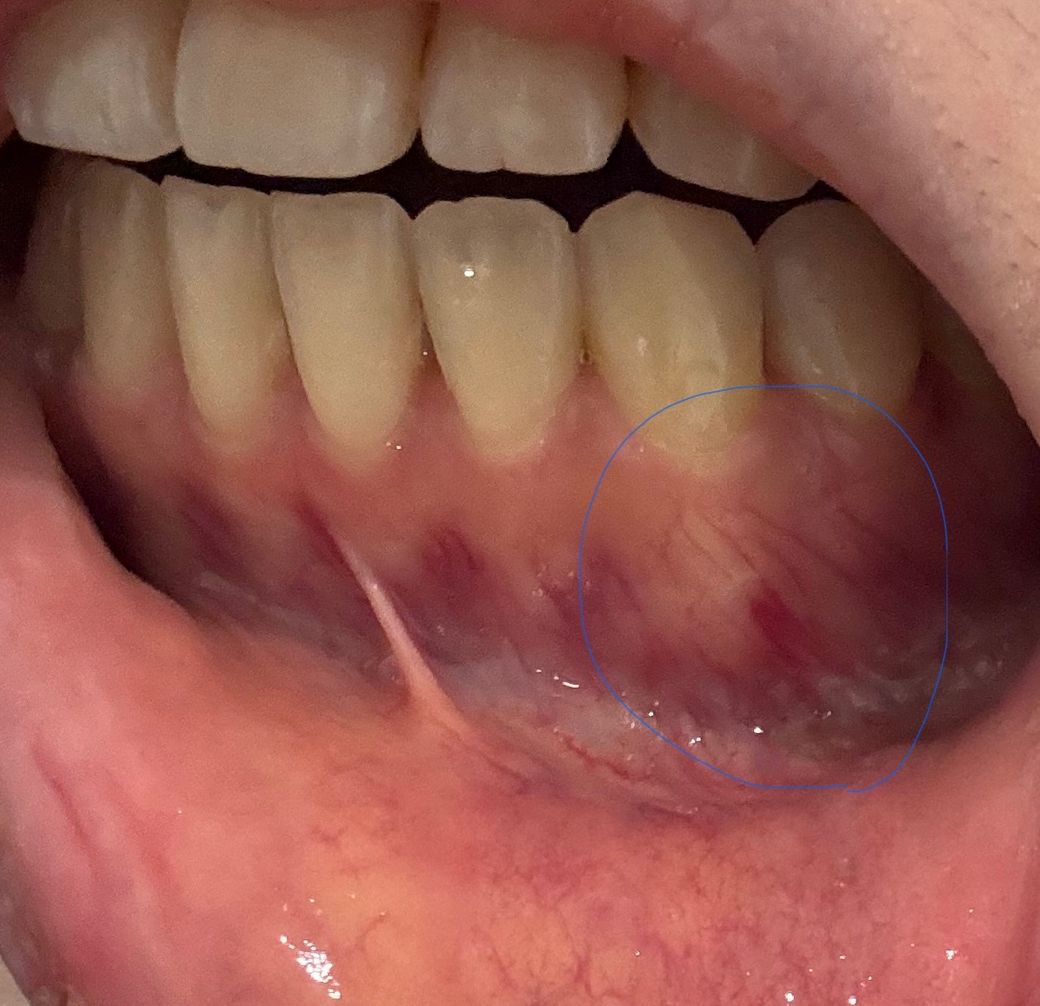

치아뿌리에 피고임 이거 신경치료해야하나요?

왼쪽아래송곳니 치아뿌리가 몇달째 주기적으로 아픈데요. 몇달전 교정치료 고무줄 사고로 7개치아 걸다가 뿌리까지 튀어나오게 돼서 너무 아파서 잠시 중단됐었거든요.

이렇게 뿌리가 튀어나오고 피가 고인것 같아보이는데 이런경우 염증인가요? 신경치료하고 크라운이나 발치하나요? 피가 고인거면 ...

주기적으로 아픈데 그냥 자연으로 나을 수 있을까요?....

단순히 잇몸이 붉게 보이는 것은 어떤 자극에 의해 그런 것으로 보이며, 이런 것은 대개 저절로 없어집니다. 신경치료하고 하는 그런 것은 아닙니다.

제가 봤을 때 현재 사진상 이상은 없어보이는데요, 필요시 CT등이 필요할 수 있겠습니다.

사진으로 봤을 경우에는 뿌리가 튀어나온 것 같아 보이진 않습니다. 해당 부의 뼈는 얇기 때문에 하얗게 보이거나 할 수 있습니다. 치아의 신경이 감염이 되어 통증을 유발하거나 한다면 신경 치료가 필요할 수 있습니다.

뿌리가 튀어나왔다기 보다는 잇몸뼈가 과증식하여 그렇게 보이는 것 같습니다

그와 별개로 치아에 지속적인 통증이 있다면 검사해보고 신경치료가 필요할 수 있습니다